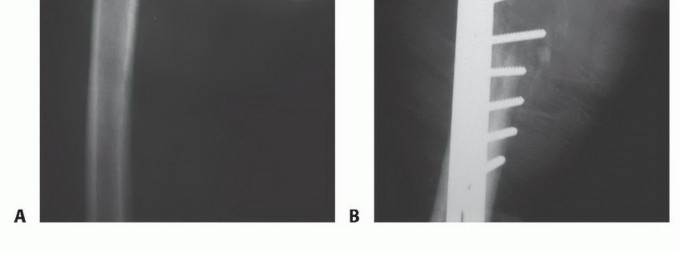

الشكل 2: أ. صورة أشعة سينية تظهر كسرًا مرضيًا في الورك لدى أنثى تبلغ من العمر 69 عامًا ولديها تاريخ معروف بسرطان الثدي. ب. أجريت عملية استبدال نصفي للورك خلال 24 ساعة من حدوث الكسر، ولكن صور الأشعة السينية بعد الجراحة أظهرت نقيلة إضافية أسفل طرف جذع الطرف الاصطناعي (ج) لم يتم اكتشافها بسبب سوء جودة صور الأشعة السينية قبل الجراحة ولأن صور الأشعة السينية للعظم بالكامل لم تُجرَ قبل الجراحة. د. بينما كانت لا تزال في المستشفى، عانت من كسر مرضي في تلك الآفة أثناء نقلها من سريرها إلى كرسي استلقاء.